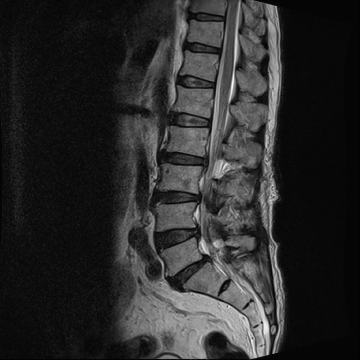

허리 디스크 수술 전·후

2021.10.19

2023.01.09

ㆍ환자 동의를 받은 자료이며, 이미지 사진은 실물과 다를 수 있습니다.

ㆍ모든 자료는 새움병원 자료입니다.